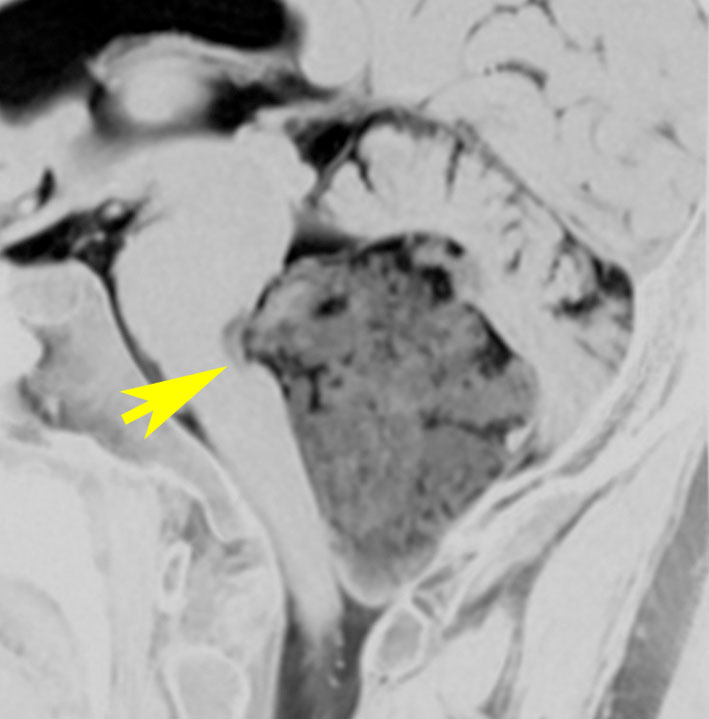

小脳橋角部の典型的な類表皮のう胞 epidermoid cyst

20代の女性が右の激しい顔面痛(三叉神経痛)で発症しました。左から順にMRIのT1強調画像,T2強調画像,拡散強調画像です。髄液と同じように見えますので脳の形の変形だけで腫瘍があることを疑います。でも,拡散強調画像では真っ白になるので腫瘍が存在していることがわかります。三叉神経は腫瘍の真ん中にあって伸びています。